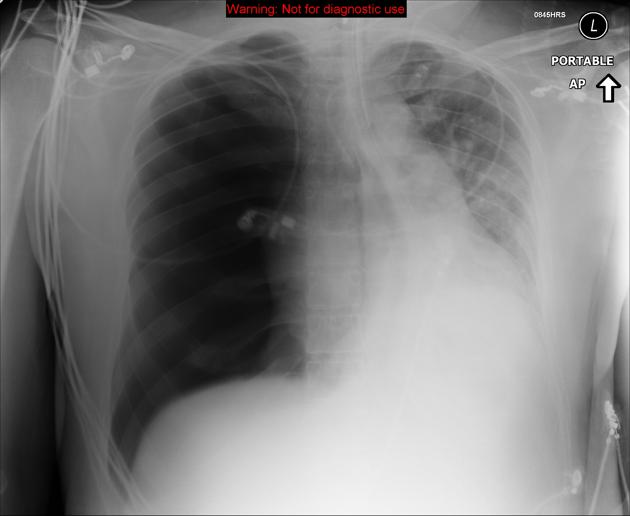

Initial CXR for the case found here:

(CXR source: https://radiopaedia.org/cases/tension-pneumothorax-9)